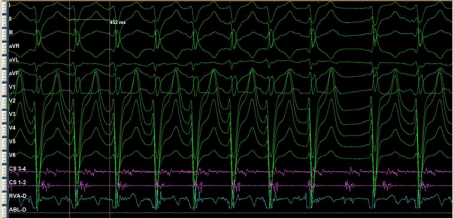

Extra stimulation with DCL=500 and PCL=350, entrainment mapping was done, sustained IART began with slow conduction zone in the systemic atrium. High density mapping with HD catheter was done slow conduction zone in the same systemic atrium was demonstrated (fig. 6).

Fig. 6: sustained IART after entrainment mapping

Mapping was performed using multipolar mapping with HD Grid (10 pole ), entrainment mapping and detailed 3D activation mapping. Entrainment was performed when the cycle length (CL) was stable (<20 millisecond beat to beat variation) and at an entrainment CL ≤20 millisecond shorter than the tachycardia cycle length. Entrainment was used in order to confirm macro–re-entry; or identify regions either “in” (PPI of ≤20 millisecond > TCL) or “near” (PPI of 20 to 40 millisecond > TCL) the re-entrant circuit in order to focus detailed 3D mapping to the region of relevance.

Figure 6